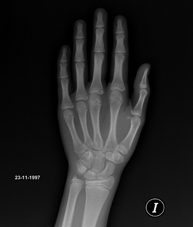

Procediment que usa els raigs X a través de la qual s'obtenen imatges de la pelvis per al seu estudi, especialment dels ossos pèlvics. - RX Edat òssia

Estudi que mitjançant una radiografia de la mà permet valorar, en funció del desenvolupament dels ossos, l'edat del pacient i determinar si existeix un retard o un creixement superior pel que correspon a la seva edat. - RX Malucs pediatria

Tècnica que usa els raigs X a través de la qual s'obtenen imatges del càvum per al seu estudi. Indicacions: dificultat respiratòria, regurgitació, otitis de repetició. - RX Edat òssia

Estudi que mitjançant una radiografia de la mà permet valorar, en funció del desenvolupament dels ossos, l'edat del pacient i determinar si existeix un retard o un creixement superior pel que correspon a la seva edat. - RX Sins paranasals